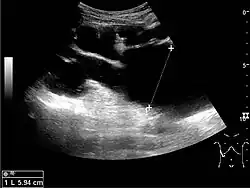

Figure 3. Measures of the kidney. L = length. P = parenchymal thickness. C = cortical thickness.[1]

Cortical thickness should be estimated from the base of the pyramid and is generally 7–10 mm. If the pyramids are difficult to differentiate, the parenchymal thickness can be measured instead and should be 15–20 mm (Figure 3). The echogenicity of the cortex decreases with age and is less echogenic than or equal to the liver and spleen at the same depth in individuals older than six months. In neonates and children up to six months of age, the cortex is more echogenic than the liver and spleen when compared at the same depth.[1]